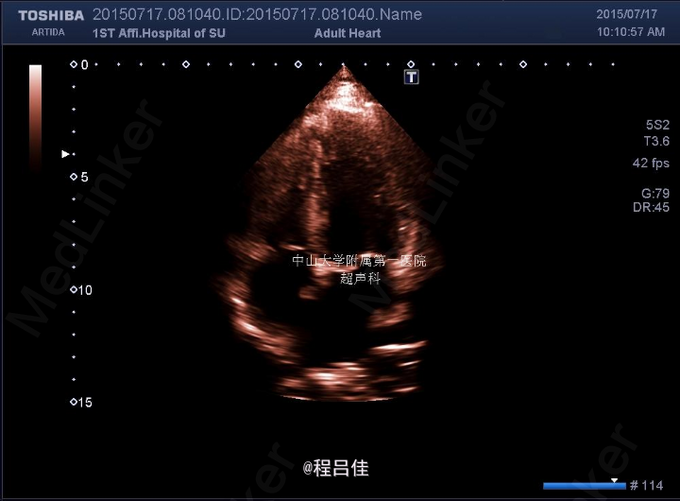

查体: 1.T37℃, P90次/分,R20次/分,BP120/80mmHg。颈软,外形对称,未见颈静脉怒张,未见血管搏动,气管偏左。右侧甲状腺II度肿大,内扪及数个结节,质硬,边界不清,无压痛,随吞咽上下移动。左侧(-)。颈部淋巴结未扪及。突眼征(-),双手震颤试验(-)。 辅查: 甲工5项正常、肺肿瘤组合(-)、血清降钙素原PCT1.31 ng/mL ↑ 、术后钙Ca 1.83 mmol/L ↓ 2.甲状腺US: 右叶甲状腺CA,向胸骨后延伸并侵犯右侧颈静脉起始段;左叶甲状腺滤泡囊肿。 双侧颈部未见异常肿大淋巴结。 3.胸片: 右上纵隔增宽,气管受压向左侧移位 4.心脏彩超:二尖瓣前叶脱垂并关闭不全(轻微),右房近上腔静脉入口处团块状回声。 5.PET-CT:甲状腺右叶及峡部肿块(向下延伸至胸骨上缘水平,邻近气管受压),代谢活跃,考虑恶性肿瘤,右侧颈内及购买起始段、右头臂静脉、上腔静脉、右心房上部节段性代谢增高,考虑癌栓形成。甲状腺左叶小结节,代谢未见异常,考虑结节性甲状腺肿或小囊肿。 6.术中冰冻快速切片报告: (左侧甲状腺)送检3.5x2.5x2cm暗红组织一块,切面暗红,无明显结节。冰冻快速切片报告镜下:结节性甲状腺肿,未见肿瘤。